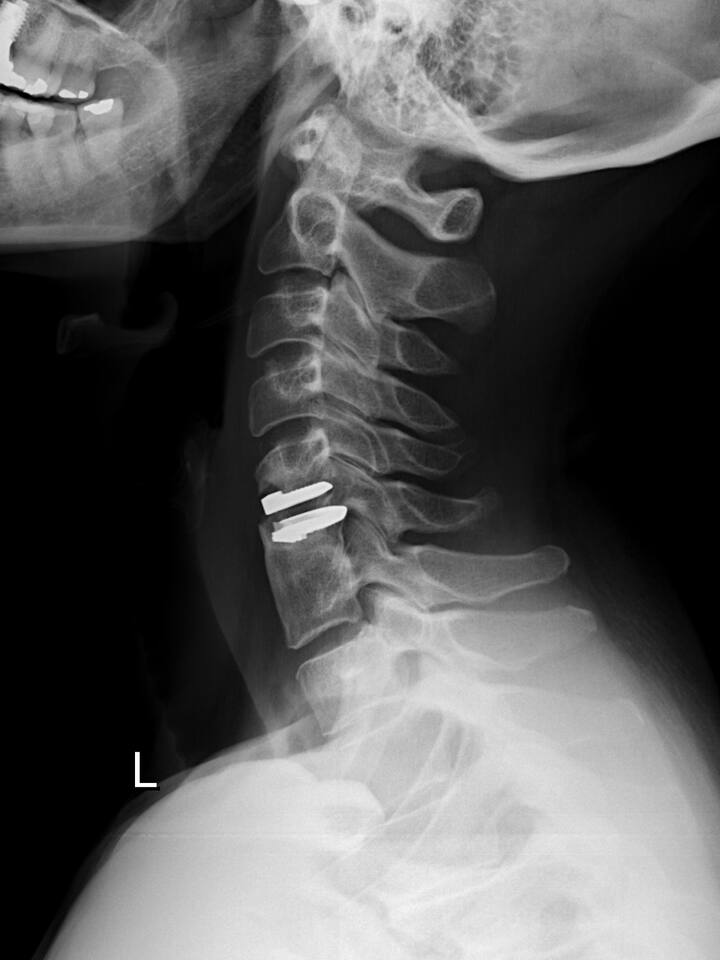

2004 schlug ihr Bernhard Jeanneret, damals Chefarzt der Wirbelsäulenchirurgie im Unispital Basel, vor, die Halswirbelsäule mit einer neuen Methode wiederherzustellen: Statt die Wirbel aneinanderzuschrauben und zu versteifen, sollte ihr eine künstliche Bandscheibe zwischen dem fünften und sechsten Halswirbel eingefügt werden. Innerhalb weniger Wochen werde sie beschwerdefrei sein.

Doch es kam anders. Nach drei Jahren musste das Implantat entfernt werden. Es hatte sich ins Rückenmark verschoben – in den Spinalkanal. Es bestand akute Gefahr, dass Ruprecht gelähmt werden könnte.

Nach der zweiten Operation hatte Heidi Ruprecht ein ungutes Gefühl. Wie war es möglich, dass fast drei Jahre lang keiner bemerkt hatte, dass die Prothese nicht wie geplant eingewachsen war? Schon 2005 hatten die Röntgenbilder gezeigt, dass sie sich verschoben hatte. Weshalb hatte man ihre Schmerzen trotzdem nicht ernst genommen? Ruprecht, promovierte Physikerin und damals Sicherheitsexpertin eines Pharmakonzerns, begann zu recherchieren. Sie verlangte Einsicht in die Krankenakte, wurde aber vom Unispital abgewimmelt. Erst als sie gegen Jeanneret Strafanzeige wegen Körperverletzung einreichte, wurden ihr nach und nach Dokumente ausgehändigt.

Bei der zweistündigen Operation vom 30. August 2004 war nicht alles optimal verlaufen. Am Vorabend hatte Heidi Ruprecht 38 Grad Fieber gehabt, am Morgen der Operation immer noch eine Temperatur von 37,6 Grad. Trotzdem wurde der Eingriff durchgeführt. Jeanneret macht heute den Anästhesisten verantwortlich, dieser habe die Patientin als «operabel» erachtet. Während der Operation wurde dann zuerst eine zu grosse Prothese eingesetzt. Das belegt der Operationsbericht.